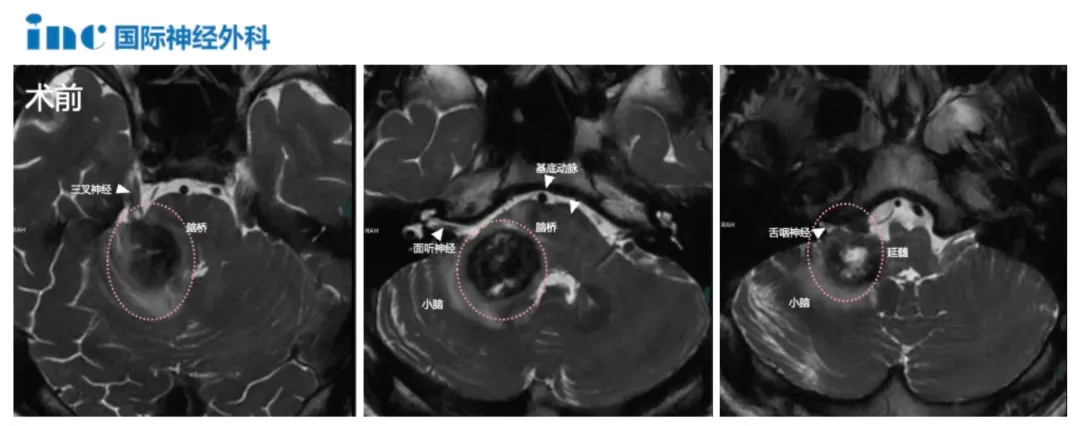

患者荣荣初期表现为间歇性头晕症状,随后出现右侧耳鸣、右侧面部麻木及舌部感觉异常等神经系统症状。当地医院影像学检查发现脑干及右侧桥臂区域存在异常信号,高度怀疑海绵状血管瘤可能。进一步检查发现小脑内复杂静脉畸形,伴较大引流静脉穿过脑桥中线区域。

脑干手术风险极高,该区域解剖结构复杂,掌管重要生理功能。海绵状血管瘤切除手术需在保留神经传导束完整性的前提下完整切除病灶,防止再出血。患者血管瘤体积较大,合并复杂静脉畸形,引流静脉穿过脑桥中线更增加手术难度。

术后三个月影像学复查显示,右侧脑桥及小脑臂内海绵状血管瘤完全切除。患者神经功能恢复超出预期,生活质量显著提高。现代神经外科技术包括术中神经导航和神经电生理监测的应用,显著提升了脑干病变手术的安全性和精准度。